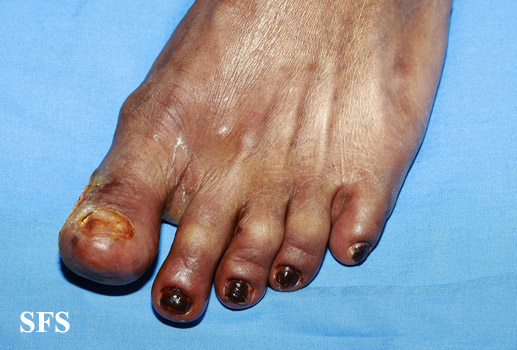

peripheral occlusive arterial disease